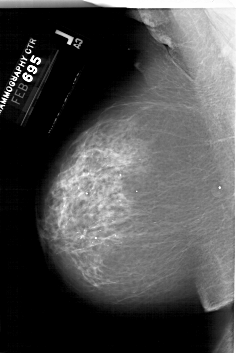

A_1999_1.RIGHT_MLO

RIGHT_MLO LINES 6196 PIXELS_PER_LINE 4306 BITS_PER_PIXEL 12 RESOLUTION 43.5 OVERLAY